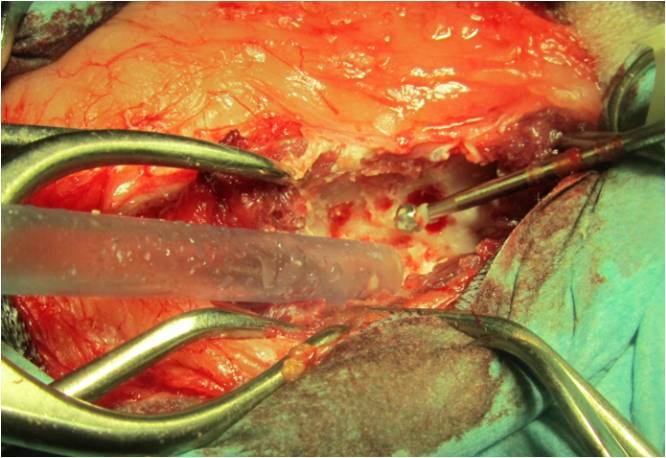

Zurück zu „Quickstep“. Gemeinsam mit den Besitzern des Hundes wurde die Entscheidung zu einem chirurgischen Vorgehen im unmittelbaren Anschluss an die computertomographische Untersuchung getroffen. Es wurde eine sogenannte Hemilaminektomie durchgeführt (Bild 4). Bei dieser Operationstechnik wird der knöcherne Wirbelkanal halbseitig auf Höhe einer Bandscheibe eröffnet, indem mittels einer Fräse und weiteren speziellen Instrumenten die Anteile des Wirbelbogens und der Zwischenwirbelgelenke entfernt werden. Dadurch bekommt man Zugang zum Rückenmark und dem vorgefallenen Bandscheibenmaterial. Dieses konnte bei „Quickstep“ dadurch entfernt werden und eine Dekompression des Nervengewebes erreicht werden. Ob und wie weit sich dieses erholt mussten nun die nächsten Wochen zeigen. Bei der Entlassung aus der Klinik konnte er selbstständig, auch wenn noch etwas unsicher in der Hinterhand, gehen. Es wurde eine strikte Ruhighaltung über acht Wochen verordnet sowie in den ersten sechs Tagen ein Antibiotikum und für zehn Tage ein Schmerzmittel.